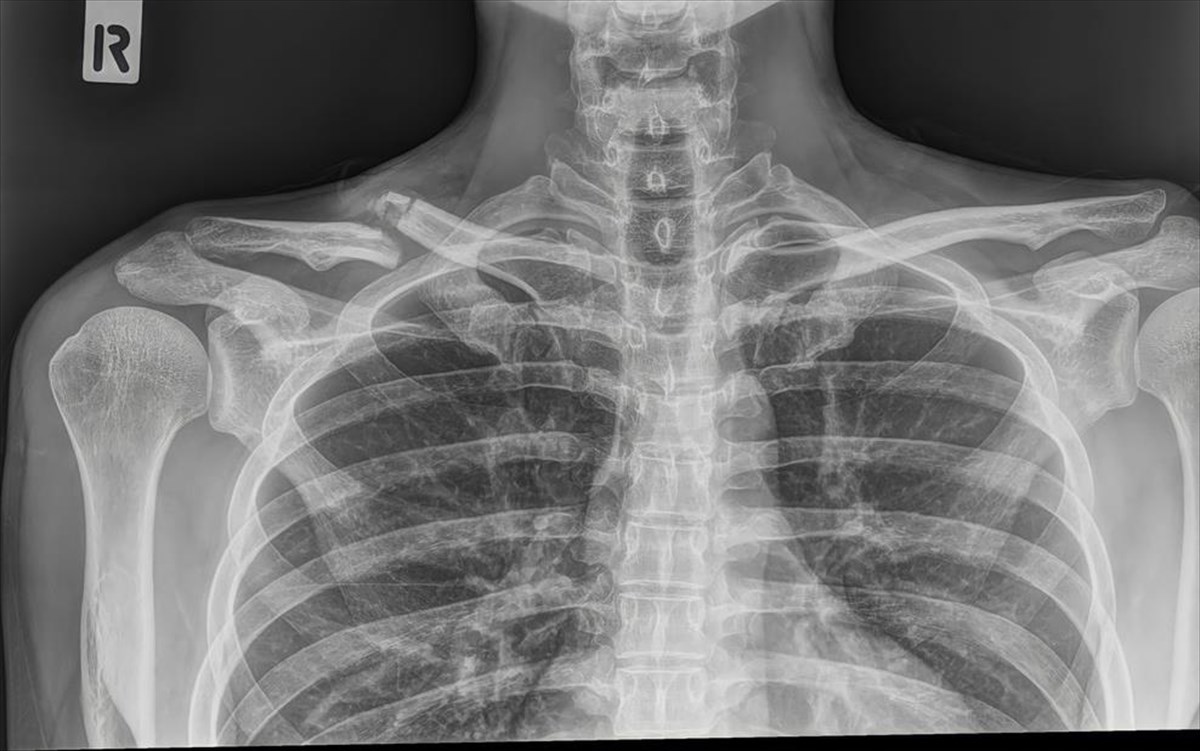

Ακτινογραφία θώρακος: 0,1 mSv (σαν να ταξιδέψετε 10 ώρες με αεροπλάνο)